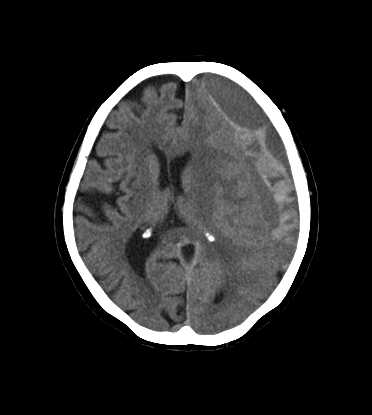

頭部

硬膜下血腫